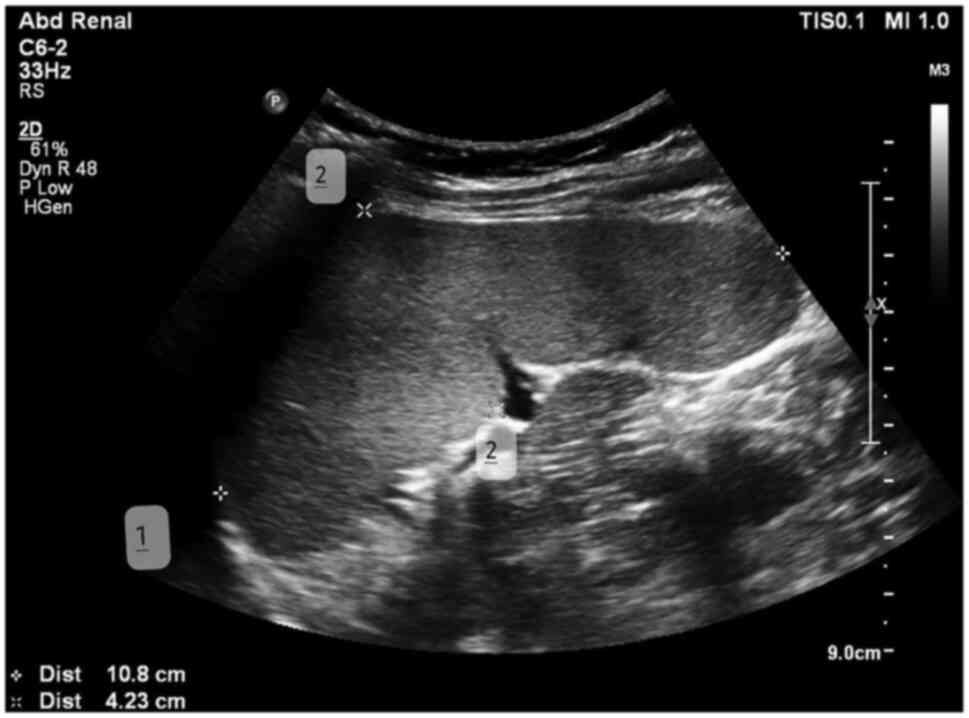

A longitudinal section (coronal oblique view) was obtained with the transducer aligned parallel to the intercostal spaces in the left upper quadrant, with the maximum diameter between superomedial and inferolateral points (length). The perpendicular diameter from the hilum to the lateral surface of the spleen (thickness) was measured in this section (Fig. 1). The transducer was then rotated 90˚ counterclockwise to image the spleen in the transverse section, and the anteroposterior diameter (width) was measured in this section (Fig. 2).

Figure 1

Spleen diameters at the level of the hilum in a longitudinal flank. In the scanned image, 1 refers to length and 2 to thickness.